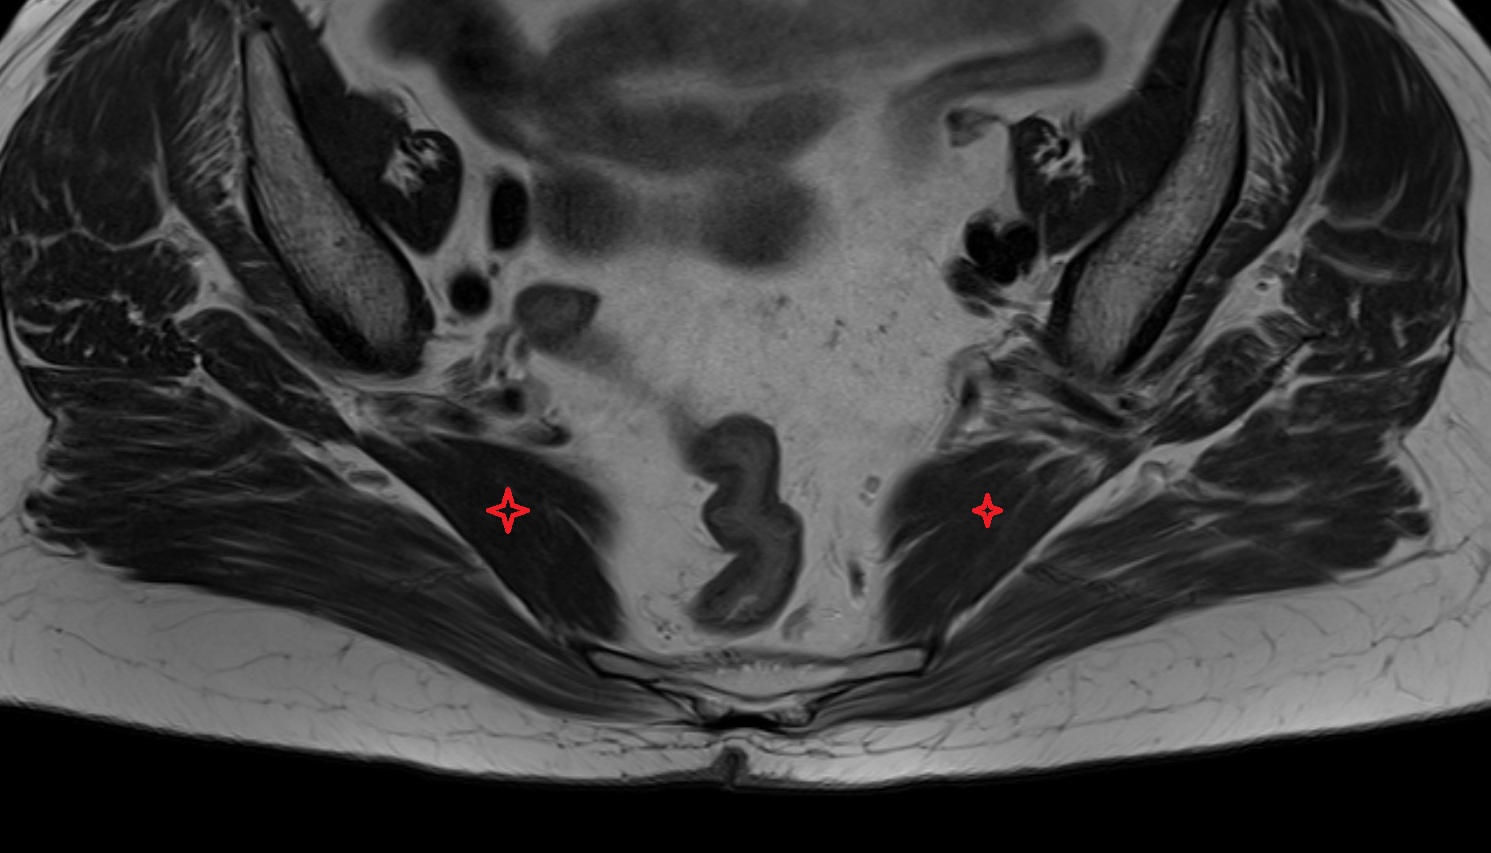

- Obturator internus muscle

- Piriformis muscle